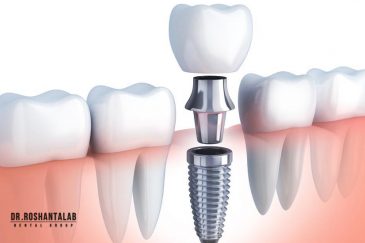

انتخاب بهترین متخصص ایمپلنت که به تکنیکهای روز دنیا مسلط باشد، تضمینکننده سلامت فک و زیبایی لبخند شماست. در کلینیک دندانپزشکی دکتر روشنطلب، ما با بهرهگیری از تجهیزات دیجیتال در ۵ شعبه فعال (تهران، اصفهان، رشت و استانبول ترکیه)، خدمات تخصصی کاشت ایمپلنت دندان را برای بیمارانی که کیفیت و دقت برایشان اولویت دارد، ارائه میدهیم. در این متد، پروسه درمان با ظرافت بالا انجام شده؛ راهکاری ایدهآل برای کسانی که به دنبال درمان بدون درد با بالاترین نرخ موفقیت هستند.

تجربه ایمپلنت دیجیتال بدون درد، سریع و ایمپلنت فوری دندان با بهره گیری از جدیدترین تکنولوژی دیجیتال در کلینیک دکتر روشنطلب؛ جایی که آرامش شما اولویت است.